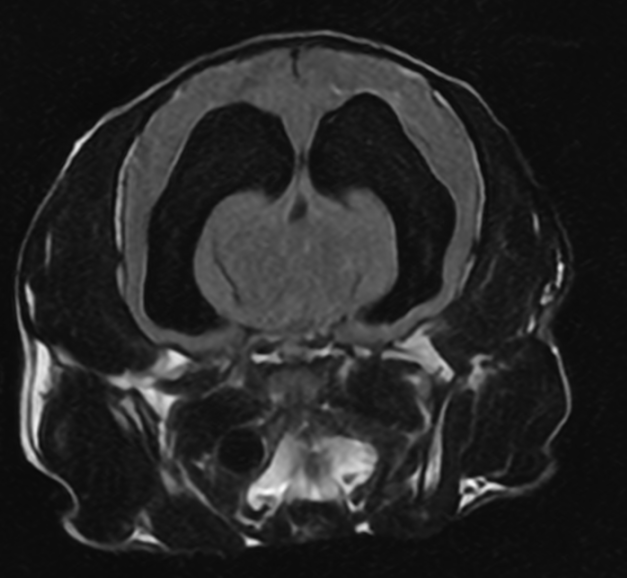

• MRI 결과

MRI에서는 아래의 복합 병변이 모두 확인되었습니다.

MRI 검사 결과 / 출처: 온숲동물의료센터

Hydrocephalus(뇌수종)

뇌척수액이 원활하게 빠져나가지 못하면서 뇌 안에 물이 점점 차 압력이 증가하는 상태입니다.